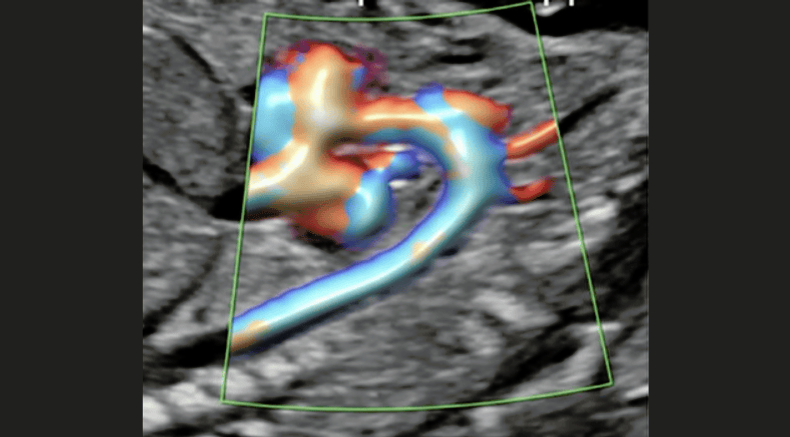

3D/4D rendering of intracardiac flow using spatiotemporal image correlation (STIC)

Chaoui, R. (2021), Evolution of fetal cardiac imaging in 30 years of ISUOG. Ultrasound Obstet Gynecol, 57: 38-42. https://doi.org/10.1002/uog.23551